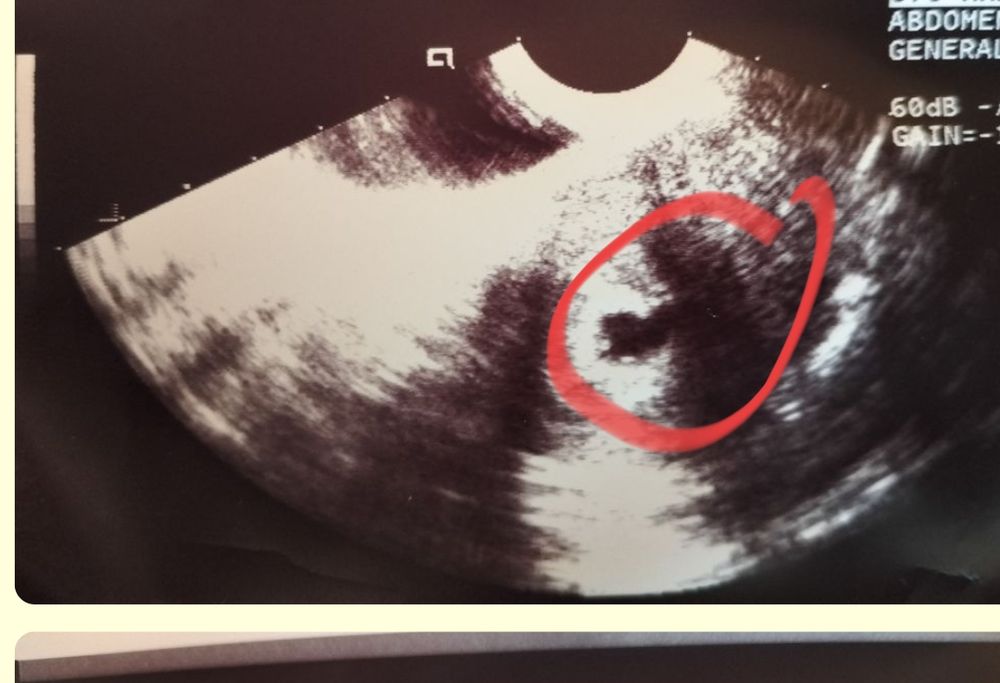

Был один малыш,а теперь двойня

Изображение Изображение Sabedoria,ну если смотреть по сниму то их двое в одном месте,хотя может срок маленький ещё и ничего толком не ясно🥰

Алина Петрова, я не совсем поняла где первый, а где второй?это первый? Изображение А второй вы обвели?